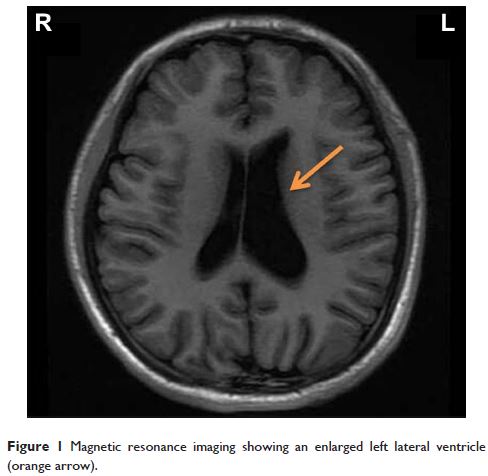

Case Report

- 作者:Jianbo Lai, Qiaoqiao Lu, Tingting Huang, Shaohua Hu, Yi Xu

- 期刊:Neuropsychiatric Disease and Treatment